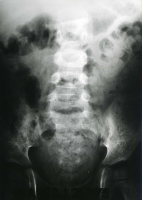

Die Abbildungen zeigen die "stumme" rechtsseitige Niere im AUR sowie die retrograde Sondierung der rechten Niere bei dem Dreijährigen (Abbildung 18).

Die operative Freilegung ergab eine deutlich vergrößerte, narbig umgewandelte Niere. Die histologische Diagnose der entfernten Niere lautete zunächst Urogenitaltuberkulose. Eingehendere Untersuchungen korrigierten dieses Ergebnis. Es bestätigte sich eine XGP. Anhand dieser Beobachtung zeigt sich die Schwierigkeit der Differentialdiagnose bei der XGP (Urogenitaltuberkulose / Tumor) (Abbildung 19).

Das Krankheitsbild entspricht einem komplizierten Harnwegsinfekt. Bei ausgedehntem Prozess ist die Niere funktionslos, im AUR "stumme" Niere (s. Abbildung oben).